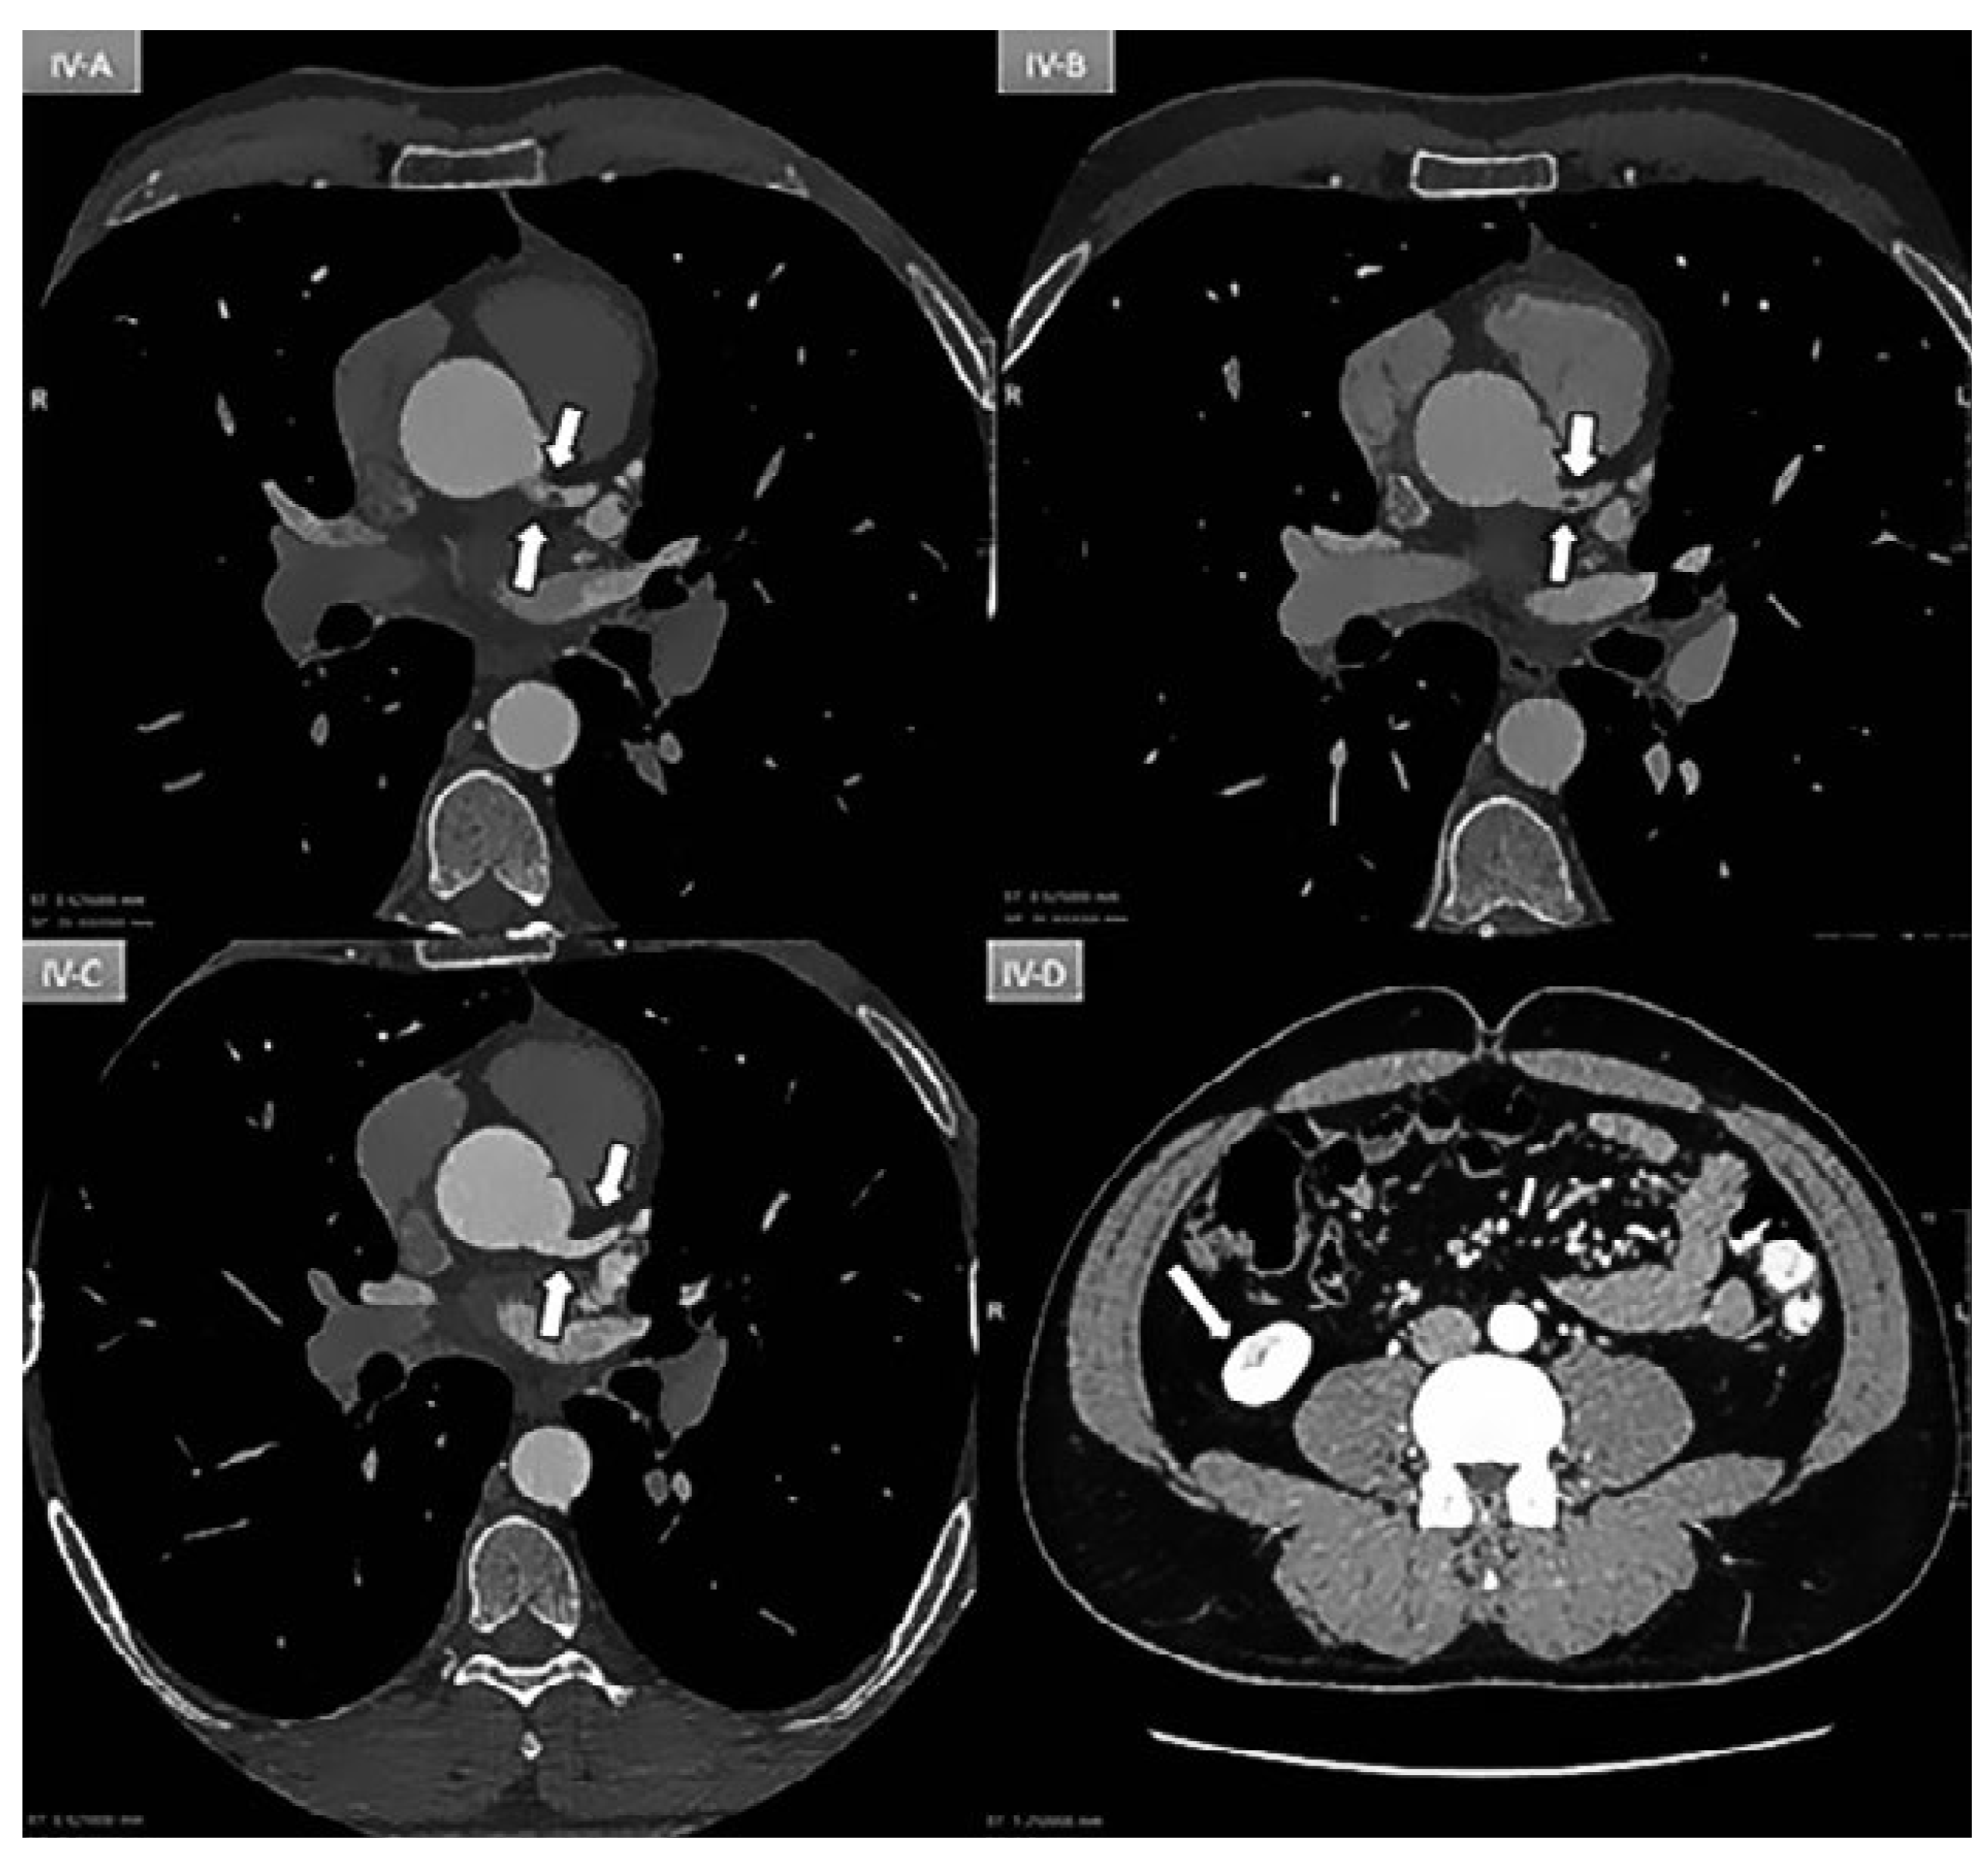

Case report